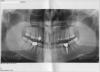

бедолага Опубликовано 13 июня, 2013 Поделиться Опубликовано 13 июня, 2013 (изменено) Здравствуйте. Я извиняюсь, надеюсь тут могут и пациенты темы создавать. Долго не ухаживал за зубами, что в итоге привело к печальной ситуации, вокруг 4х передних зубов на нижней челюсти, те что между клыками (извините нумерацию не знаю) здорово осела кость как мне сказал хирург. Вобщем сказал делать подсадку костной ткани. Название материала не помню, но вроде бы что-то на основе бычьей кости. Говорил что в лучшем случае нарастет где-то 1мм кости, что процесс может занять от 6 месяцев до года, потом можно будет думать, нужна или еще подсадка, ессно сказал что никаких гарантий и так далее, я понимаю хирургия это не ремонт магнитофонов или что-то в этом роде.Так вот хочу чтобы кто-то посмотрел и сказал на сколько все плохо, делать ли подсадку костной ткани. Болезненная ли это процедура и на сколько тяжела в исполнении, это очень важный момент, так как мне тут кое-кто наговорил не очень хороших отзывов о хирурге который будет мне делать это. Снимок прилагается. Буду благодарен если кто-то ответит побыстрее, на завтра назначена процедура, но если что я могу отменить еще. Спасибо за помощь. Изменено 13 июня, 2013 пользователем бедолага Ссылка на комментарий

бедолага Опубликовано 14 июня, 2013 Автор Поделиться Опубликовано 14 июня, 2013 для оценки уровня кости нужен панорамный снимок Он видел и ситуацию во рту.+ Панорамный снимок дает общее представление,Сделайте снимок, лишним не будет.. Сделал снимок. Заодно пошел там проконсультироваться к другому хирургу. Пришел говорю, вот так и так кость осевшая, другой хирург говорит что надо наращивать (подскаживать) костную ткань, так как зубы не на достаточно большой глубине в кости и следовательно из-за большого рычага кость будет продолжать осаживаться.. Он потрогал зубы, шатаются ли или нет, спросил есть ли жалобы какие-то, посмотрел снимок и говорит что хоть кость и осевшая (она говорит при нашей экологии у 70% такая) сказал делать ничего не надо, только массажировать десну два раза в день щеткой. Еще говорил что чтобы подсаживать кость надо делать полную опперацию, сказал для этого надо удалять все нервы в этих 4х передних зубах О_О, а другой хирург мне ничего не говорил вообще такого, говорил что просто отслаивается десна, чистится все и ложиться материал туда, потом заживается и все. но этот хирург начал рассказывать про удаление нервов, шинирование и все такое. Объясните зачем удалять нервы в этих зубах если костный материал ложится просто на на кость под десной??? меня это испугало короче. С одной стороны рад что не все так плохо, а с другой стороны расстроен что уже ничего сделать нельзя, десна опущена, у меня треугольники между этими зубами, выглядит ужасно, боюсь иногда даже разговаривать с кем-то, улыбаться (зубы скалить) во всю тоже стесняют... Вобщем, что делать подскажите? ничего? или можно все таки вернуть кость и десну как-то? хочу улыбаться во всю снова. materialимя существительное: material, stuff, fabric, matter, stock Ссылка на комментарий

бедолага Опубликовано 14 июня, 2013 Автор Поделиться Опубликовано 14 июня, 2013 (изменено) еще мне кажется у меня имплант криво как-то стоит, хотя он не беспокоин, не шатается, ничего. под имплантом кость вогнутая, так как там зуба не было лет 8, наверное из-за этого. хирург сказал что все нормально вроде... Изменено 14 июня, 2013 пользователем бедолага Ссылка на комментарий